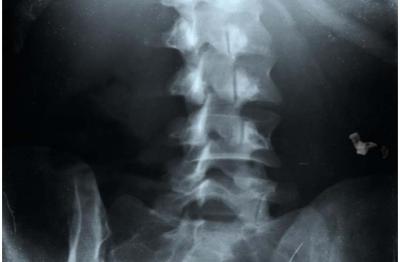

Surgeons use various methods to track sponges during operations. The most common is manual sponge counts by a nurse, but more sophisticated methods include the radio-frequency tagged sponges used in the UNC study, X-ray of the abdomen and bar-coded sponges. The UNC investigators did not include bar-coding systems in their study. Human error involved with manual counting and X-ray interpretation were the impetus that resulted in the studies inception, Rupp reported.

The RF-tagged system in the UNC study has the same technology found in the clothing tags used in retail store tracking systems and in microchips embedded in pets. During surgery, a nurse passes a wand over the patient's body to pick up readings from the RF tags. Newer versions have detection hardware built into the mat the patient lies on. "RF detection is not going to replace counting in the operating room, but it can be used as an adjunct because, from what we're seeing in the preliminary data, it adds a lot to the safety of the procedure," Rupp said.